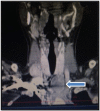

We report a case of a 29-year-old woman who suffered from severe bilateral inguinal pain and left mandibular mass. CT scan showed innumerable expansile osteolytic bone masses on the iliac wings, femur, ribs and vertebral bodies, diffuse skeletal osteopaenia, calyceal lithiasis on the right kidney and a left thyroid mass. Ionised calcium and intact parathyroid hormone (PTH) were elevated. Parathyroid sestamibi scan showed a hyperfunctioning left inferior parathyroid gland. Biopsy of the left mandibular mass was consistent with brown tumour. The patient underwent parathyroidectomy of the enlarged parathyroid gland. Final histopathology, however, revealed parathyroid carcinoma, 4.7 cm in widest dimension, with capsular and vascular space invasion. The patient underwent repeat surgery, specifically, left thyroid lobectomy, isthmectomy and central node dissection. Intact PTH decreased from 681.3 to 74 pg/mL (normal range: 10-65) 24 hours postoperatively. Follow-up at 6 months showed normal serum calcium levels, size reduction of bone lesions and improvement of quality of life.